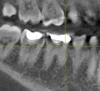

baroccco Опубликовано 16 октября, 2013 Поделиться Опубликовано 16 октября, 2013 на 3д снимке видно что-то вроде вторичного кариеса. Зуб иногда дает о себе знать неприятными ощущениями. Будут ли удалять нерв при перепломбировке? Откуда берется вторичный кариес? Ссылка на комментарий

baroccco Опубликовано 16 октября, 2013 Автор Поделиться Опубликовано 16 октября, 2013 похожая история с другой стороны.На 2д ортопантомограмме ничего такого не видно. Ссылка на комментарий

DmitrySH Опубликовано 16 октября, 2013 Поделиться Опубликовано 16 октября, 2013 Прилегание пломб на КТ не смотрят. Данная картинка не соответствует реальности. Ссылка на комментарий

DmitrySH Опубликовано 17 октября, 2013 Поделиться Опубликовано 17 октября, 2013 так речь была про очный осмотр без снимков что вы имеете ввиду под "не соответствует реальности"? На КТ пломбировочный материал создает тень. На прицельном снимке не будет таких очагов затемнения в зубе Ссылка на комментарий

baroccco Опубликовано 18 октября, 2013 Автор Поделиться Опубликовано 18 октября, 2013 На КТ пломбировочный материал создает тень. На прицельном снимке не будет таких очагов затемнения в зубеа почему материал создает тень только в тех местах, где мог бы быть интерпроксимальный кариес? Ссылка на комментарий

red_butler Опубликовано 18 октября, 2013 Поделиться Опубликовано 18 октября, 2013 а почему материал создает тень только в тех местах, где мог бы быть интерпроксимальный кариес? Если выставить срезы по другому, "тени" будут в других местах. Решение о необходимости эндодонтического лечения принимается на основании комплекса объективных данных, жалоб и сбора анамнеза (истории). А Rg, в т. ч. И Кт - дополнителный способ исследования 2 Ссылка на комментарий